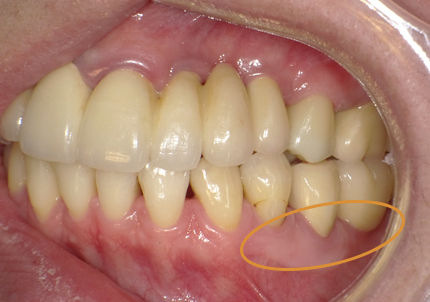

3.左下遊離歯肉移植術(F.G.G)(2009年6月)

再生療法後に付着歯肉消失の為、左下4・5・6・7番の付着歯肉の獲得を目的に遊離歯肉移植術(F.G.G)を選択する

口蓋より角化歯肉を採取して骨膜上に縫合する